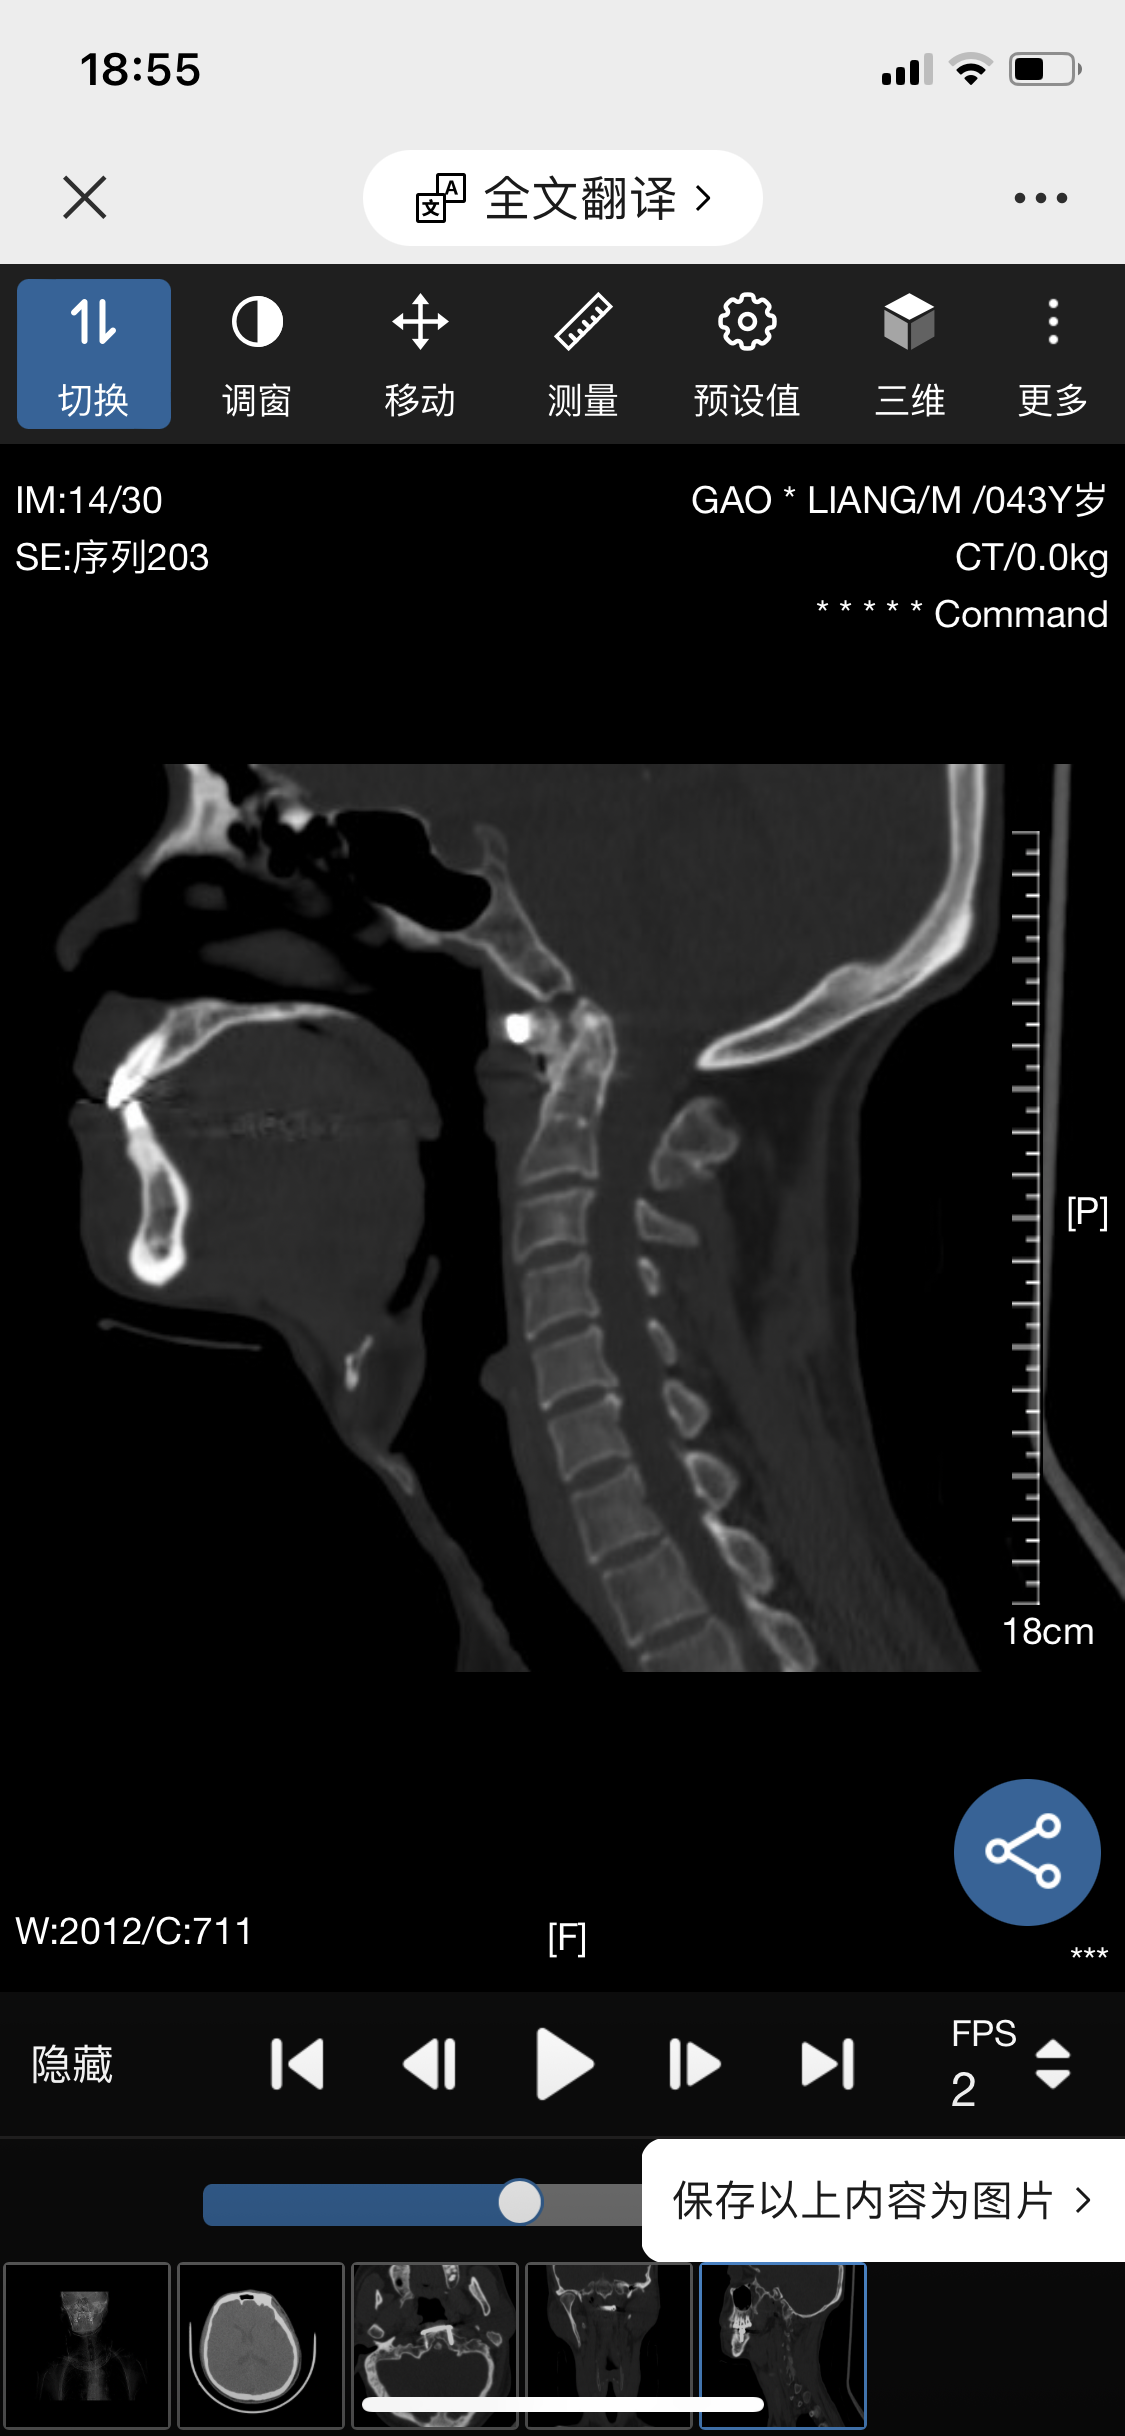

• 诊断:寰枢椎脱位

• 影像: